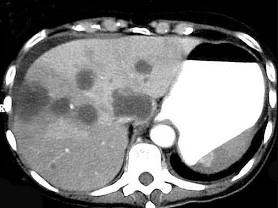

继发性肝癌诊断的关键是 ( )A、行CT检查B、测定血清甲胎蛋白C、行肝动脉造影检查D、行放射核素扫描E、查清原发癌灶

问题 继发性肝癌诊断的关键是 ( )

选项 A、行CT检查 B、测定血清甲胎蛋白 C、行肝动脉造影检查 D、行放射核素扫描 E、查清原发癌灶

答案 E